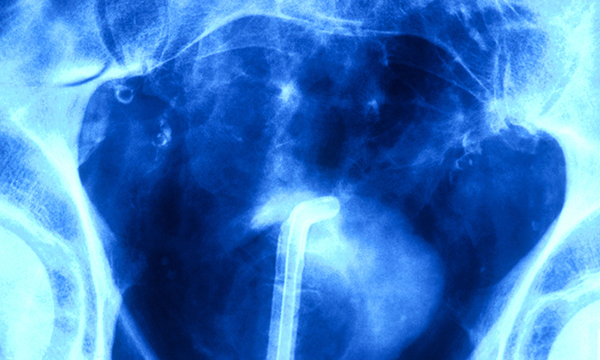

Self-management of long-term urinary catheters can be challenging for patients, and recurrent catheter blockages may cause concern among patients, carers and healthcare professionals. Catheter blockages are a significant challenge for nurses practising in community settings, because frequent and unplanned catheter changes can be costly to healthcare services in terms of time and resources. This article details evidence-based recommendations for the assessment and diagnosis of catheter blockages, as well as the identification of risk factors. It also explains the interventions that can be used to prevent and manage catheter blockages and describes the role of the nurse in supporting patients with a long-term catheter in situ in community settings.